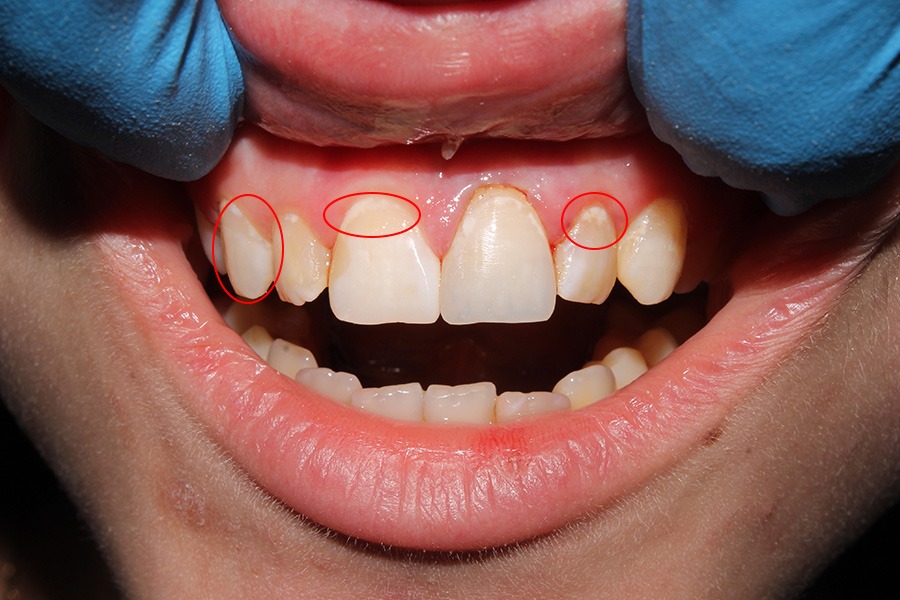

2.1 Sâu răng độ 1 (Mức độ nhẹ)

Sâu răng độ 1 là sâu men răng và là mức độ nhẹ nhất của bệnh sâu răng. Axit sinh ra từ bệnh nền hoặc thói quen vệ sinh răng miệng kém là nguyên nhân gây sâu răng ở giai đoạn này. Dấu hiệu dễ nhìn thấy nhất ở giai đoạn này chính là sự xuất hiện của những vệt trắng đục hoặc lốm đốm màu đen (hoặc nâu) trên bề mặt răng. Ở giai đoạn này, bệnh nhân sẽ rất dễ chủ quan vì vẫn chưa cảm thấy đau nhức hay khó chịu kể cả khi ăn thực phẩm cay, nóng hay lạnh.

Cách xử lý giai đoạn sâu răng ở giai đoạn này khá đơn giản, bạn nên thường xuyên răng miệng một cách cẩn thận và tốt nhất nên đến nha khoa để loại bỏ vôi răng định kỳ 6 tháng/lần để tránh bệnh chuyển biến sang sâu răng độ 2.

Sâu răng độ 1 (Mức độ nhẹ).